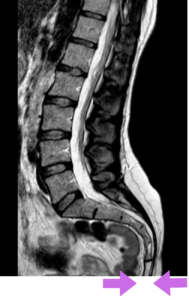

Stuitpijn is pijn rond het stuitje (coccyx), meestal net achter de anus, die vooral toeneemt bij zitten of bij druk op de stuit.

Stuitklachten kenmerken zich vaak door pijn bij zitten, opstaan en bij directe druk op de stuit. De klachten kunnen variëren van mild tot zeer beperkend in het dagelijks functioneren. Op de uitgebreide pagina over stuitpijn wordt dieper ingegaan op het ontstaan en het beloop van deze klachten.